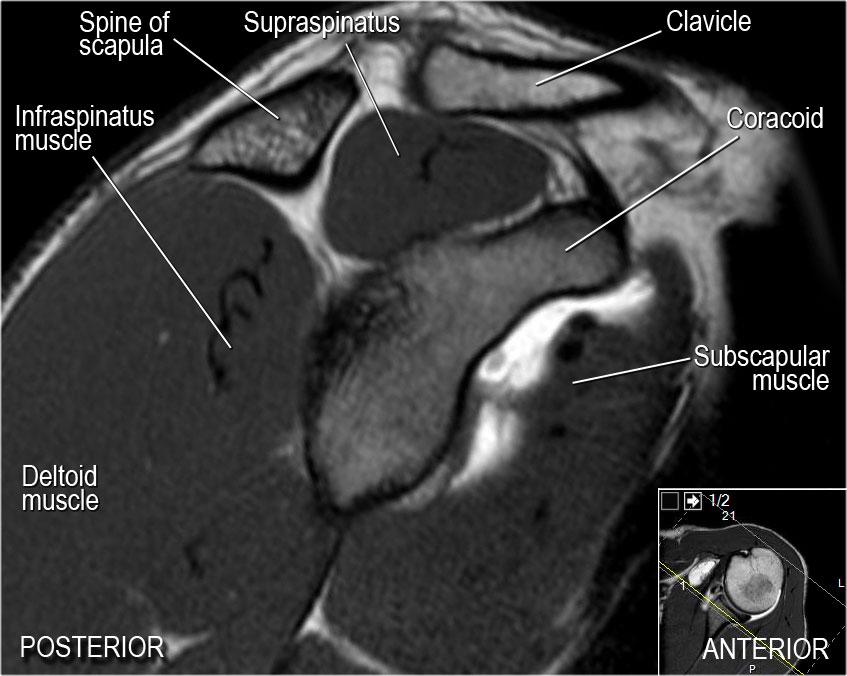

Giải phẫu mặt cắt đứng dọc và danh sách kiểm tra

- Lưu ý các cơ chóp xoay và tìm kiếm dấu hiệu teo cơ.

- Lưu ý dây chằng ổ chảo-cánh tay giữa (MGHL), có đường đi chéo qua khớp, và đánh giá mối liên quan với gân cơ dưới vai.

- Đôi khi ở mức này có thể quan sát thấy rách sụn viền ở vị trí 3-6 giờ.

- Đánh giá điểm neo gân cơ nhị đầu.

- Lưu ý hình dạng của mỏm cùng vai.

- Tìm kiếm hội chứng chèn ép do khớp cùng-đòn. Lưu ý khoảng gian chóp xoay với dây chằng quạ-cánh tay.

- Tìm kiếm rách gân cơ trên gai.